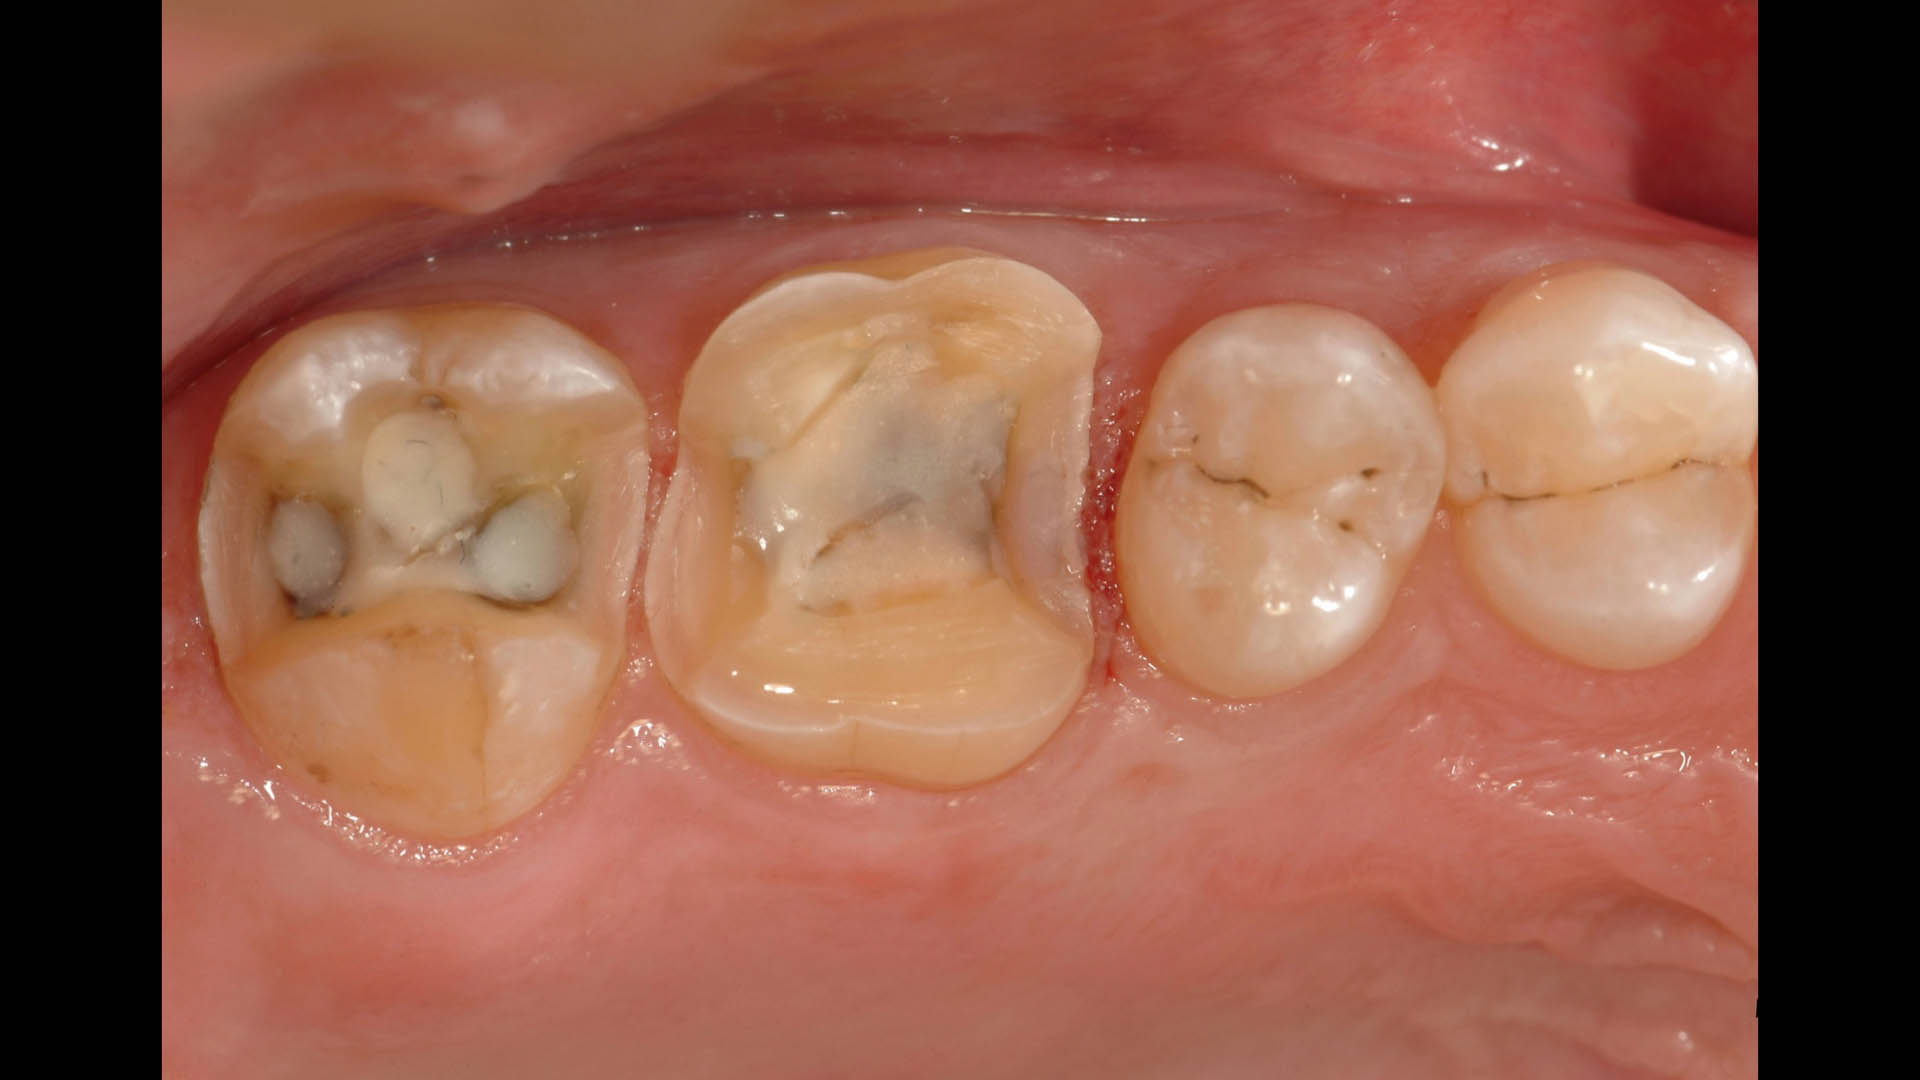

Take a glimpse into the magic of Coral Gables Dentistry through our before and after pictures. See firsthand the incredible smile makeover transformations that have brought confidence and joy to our patients.